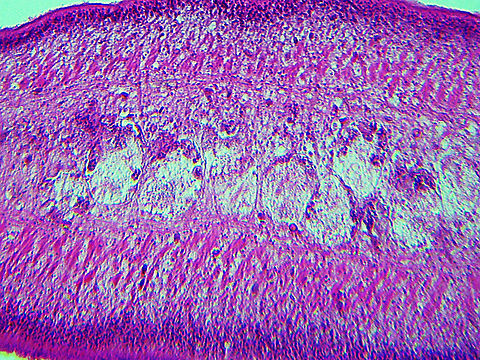

''Taenia pisiformis'', commonly called the rabbit tapeworm, is an endoparasitic tapeworm which causes infection in lagomorphs, rodents, and carnivores. Adult ''T. pisiformis'' typically occur within the small intestines of the definitive hosts, the carnivores. Lagomorphs, the intermediate hosts, are infected by fecal contamination of grasses and other food sources by the definitive hosts. The larval stage is often referred to as ''Cysticercus pisiformis'' and is found on the livers and peritoneal cavities of the intermediate hosts. ''T. pisiformis'' can be found worldwide.